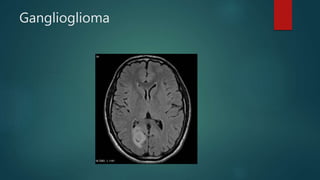

Ganglioglioma